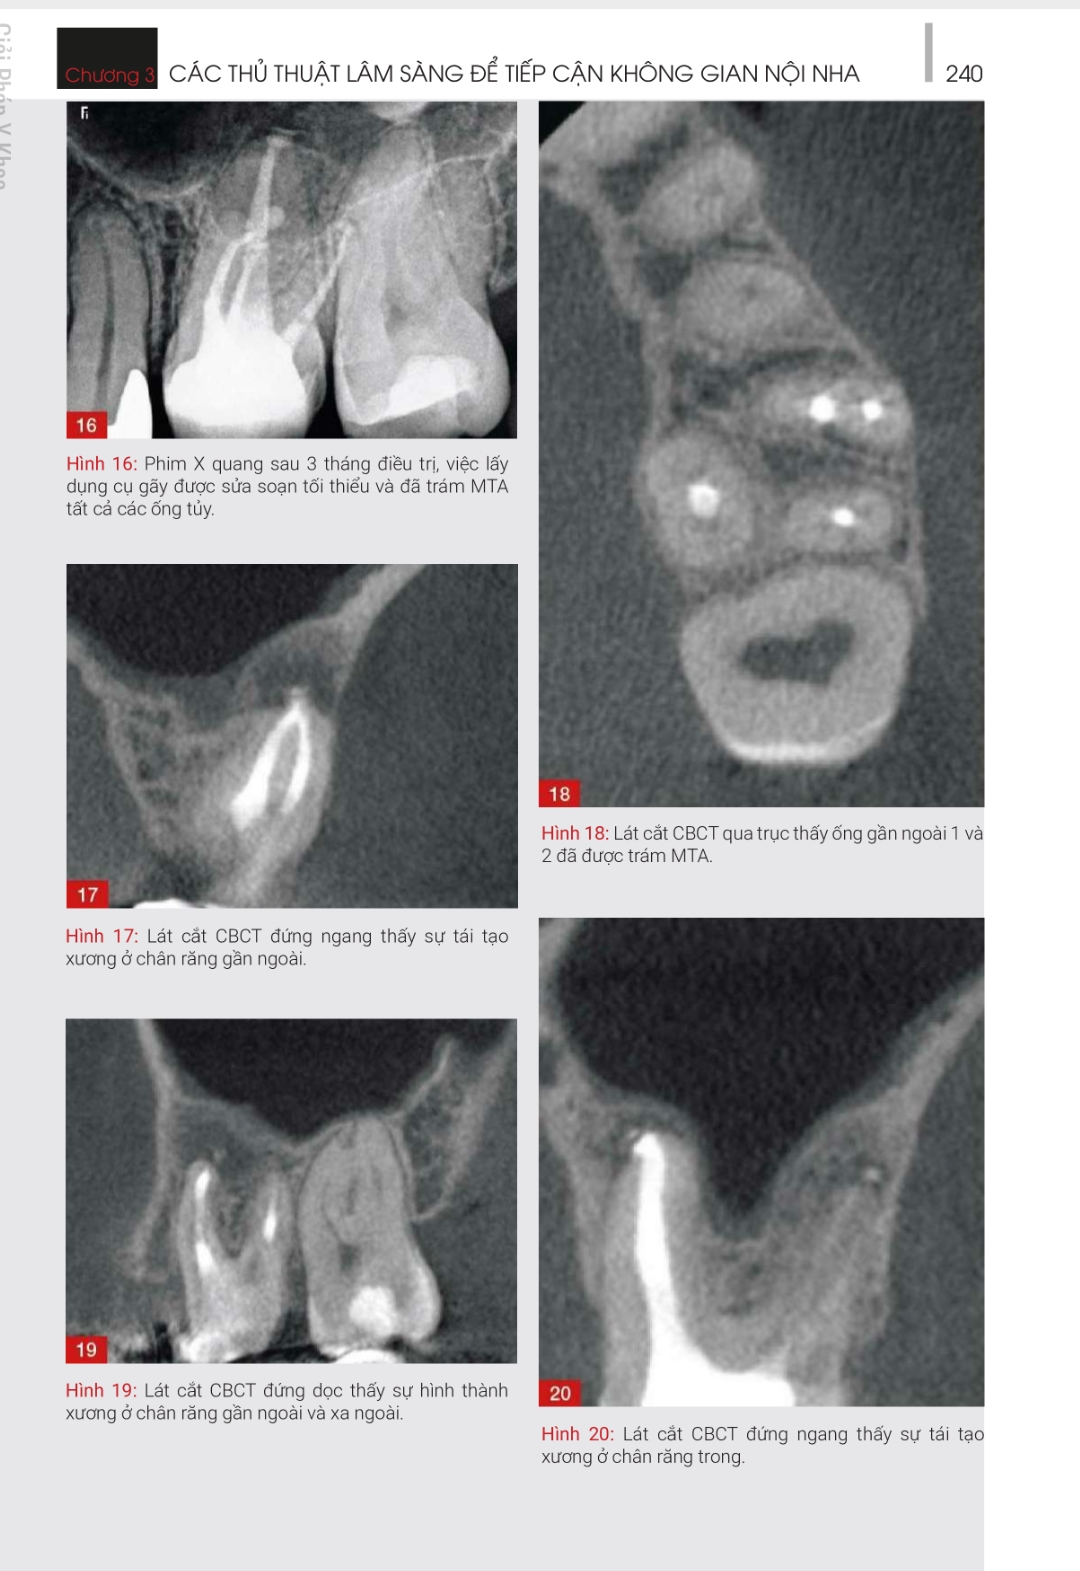

ĐIỀU TRỊ LẠI – NHỮNG GIẢI PHÁP SANG THƯƠNG QUANH CHÓP NGUỒN GỐC TỪ NỘI NHA